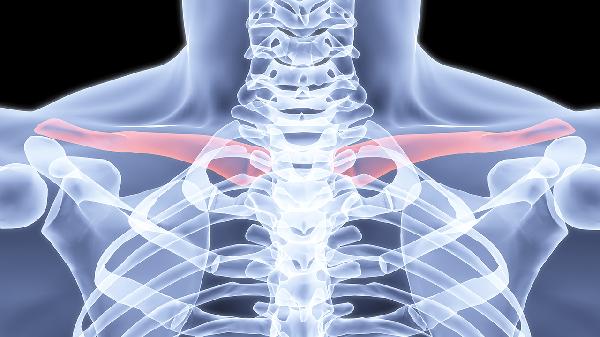

4、胸锁关节紊乱:

胸锁关节脱位或退行性变可能引发局部隐痛,关节活动时有弹响感。需通过X线或CT确诊,轻症可通过关节复位和固定治疗,反复脱位需手术修复。